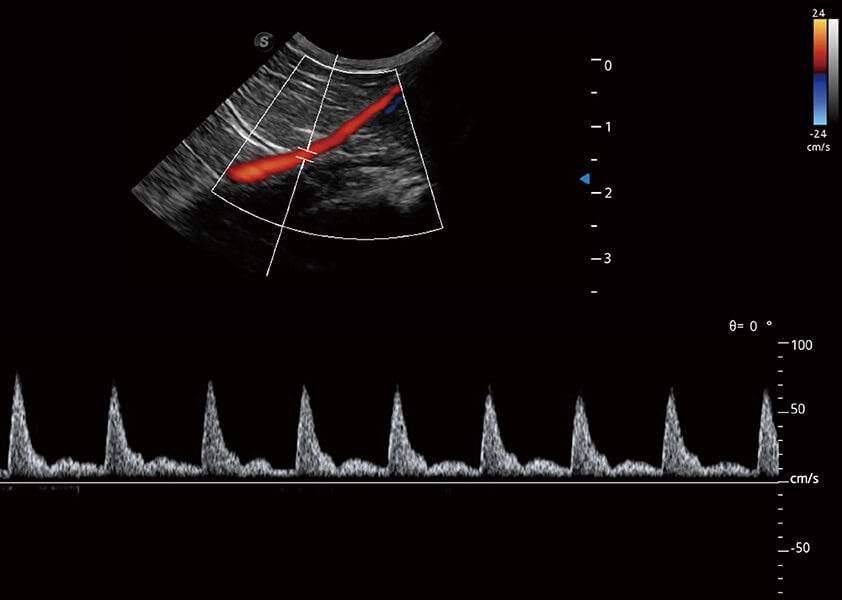

ProPet 60 作为一款高端台式动物超声设备,为动物医生的日常诊断提供了一系列贴合动物临床需求、解决临床实际问题的高级成像功能。凭借全系列高清探头,满足医生对腹部、心脏、生殖、浅表、肌骨等成像的所有需求,切实帮助您提升检查效率,提高诊断信心。

动物是人类最亲密的朋友和最值得信赖的伙伴。16877太阳集团也一直致力于探索动物专用的超声影像解决方案。 全新推出的ProPet系列,是16877太阳集团在动物超声影像智能化、专业化、精准化的一次跨越式革新。动物不能用言语来表述自己的不适,通过超声影像,ProPet系列搭建了动物医生与不同物种沟通的“桥梁”,为动物医生注入了“治愈之力”。